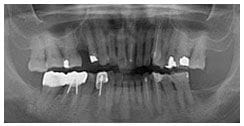

X 光片

術前X光片